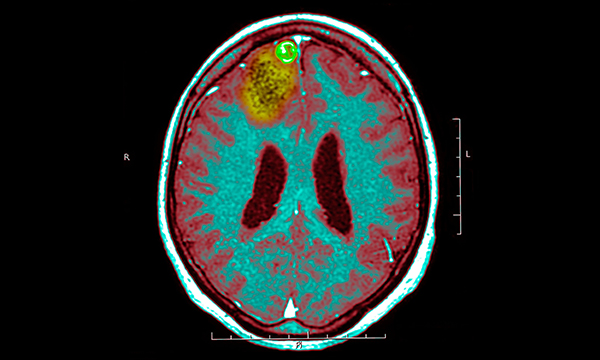

Homeless people are up to eight times more likely to have epilepsy than the national average. David Parker-Radford, homeless health project manager at the Queen’s Nursing Institute explains why a guide on how to bridge the gap is needed now more than ever before